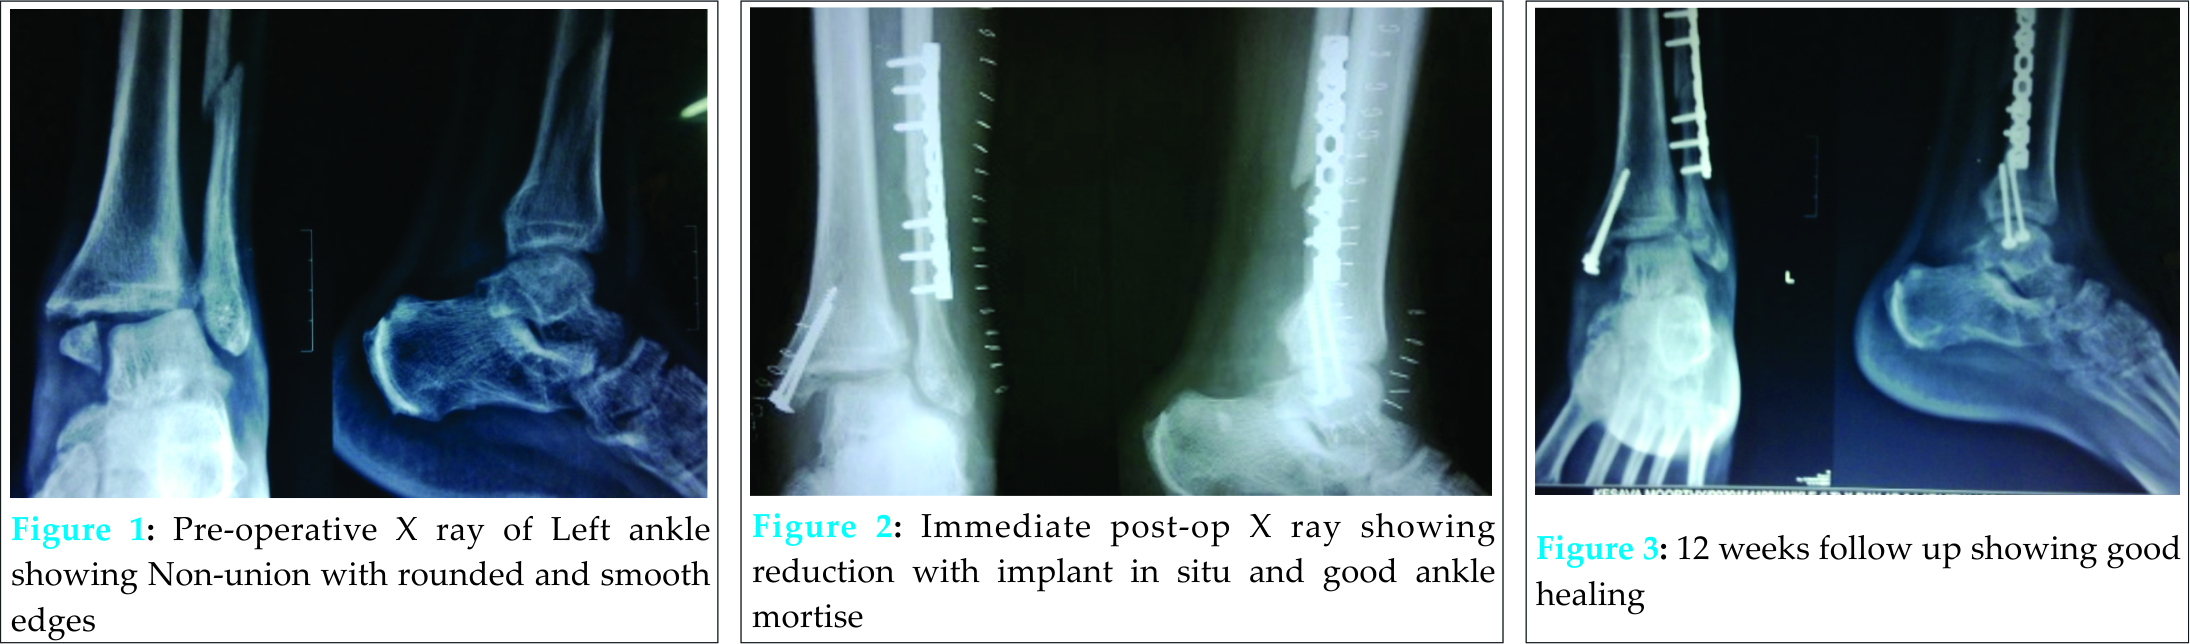

The study was conducted between September 2010 to August 2013. Eleven patients who presented to us with non-union of bimalleolar fractures were included. There were 7 males and 4 females. The average age was 48.63 years (31-56 years). The average time of presentation since injury was 18.45 weeks (range 14-22 weeks). All patients were subjected to internal fixation with plate and screws for the fibula. Nine patients had screw fixation for the medial malleoli and two patients had tension band wiring (TBW). Additional bone grafting harvested from the distal femur was used in 3 cases to augment fixation. Six patients were immobilized with a below knee plaster cast for 12 weeks. All patients were started on non –weight bearing walking with walker support from post-operative day ‘1’. Wound dressings, antibiotic prophylaxis and suture removals were done as per standard protocols in all but two patients. All patients were followed up at 4, 8, 10, 12 weeks and weekly thereafter till radiological evidence of union[Fig 2 & Fig 3] was made. The functional assessment was tabulated using the Karlsson and Petersson scoring system.

All 11 patients were followed up till the end of the study. Ten of the 11 patients went on to union at an average of 13.8 weeks (range 12-17 weeks). Patient No. 5 (Table1)had a comminuted fracture of the medial malleoli which was treated by tension band wiring which failed to unite with bone resorption seen on follow-up radiographs. She was a diabetic with a BMI of 31. She was offered a revision fixation with bone grafting but she refused for surgery. She was put on a Ankle-Foot Orthoses (AFO) and mobilized. Although she had satisfactory mobility with a walker support her functional outcome was poor. Four patients had a painful scar which improved at the end of 4 weeks. The two patients who had delayed wound healing and delayed suture removal were both females with BMI > 30 with diabetes. The functional ankle score was excellent in 6 [Fig 4 & Fig 5], good in 3, fair in one and poor in one.